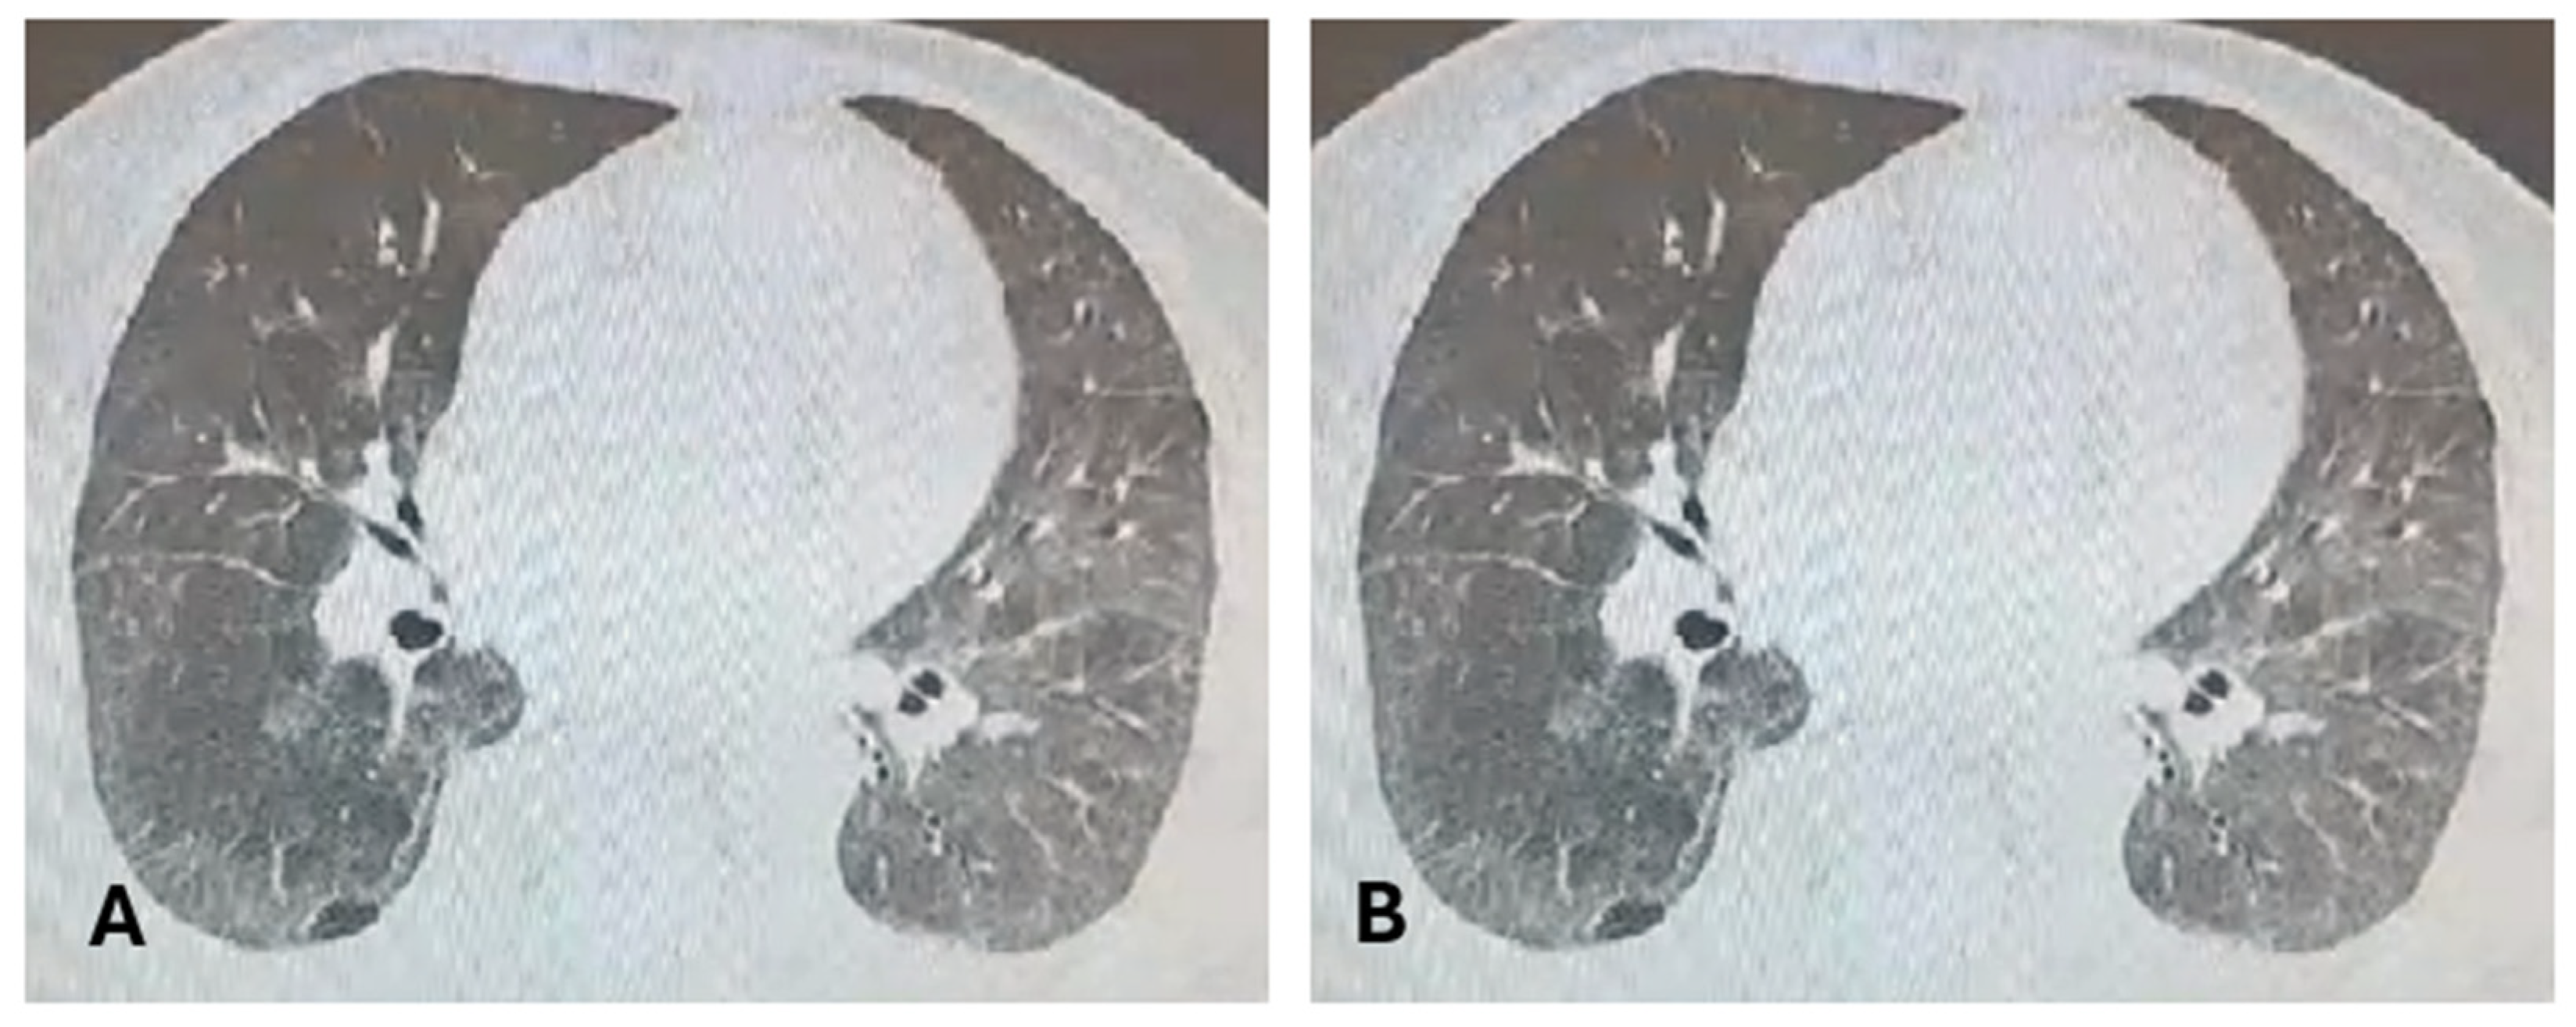

5. Clinical and Paraclinical Presentation